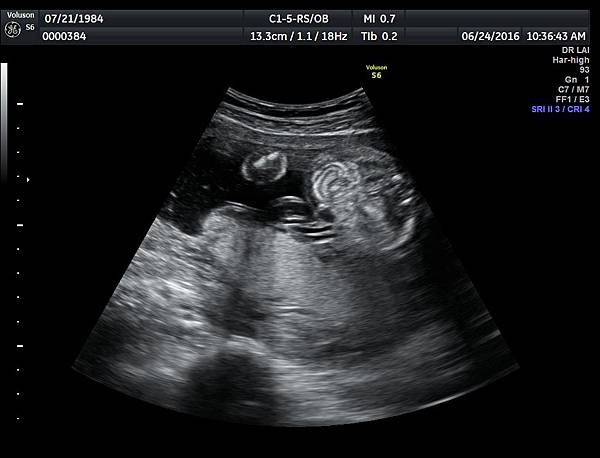

6月24日在我的診所,我幫一位懷孕22週31歲的孕婦看高層次超音波,發現胎兒的腸子很白,形狀也特別的怪( 附圖 1~12 ),我建議她做進一步相關的檢查,包括抽羊水檢查等等。